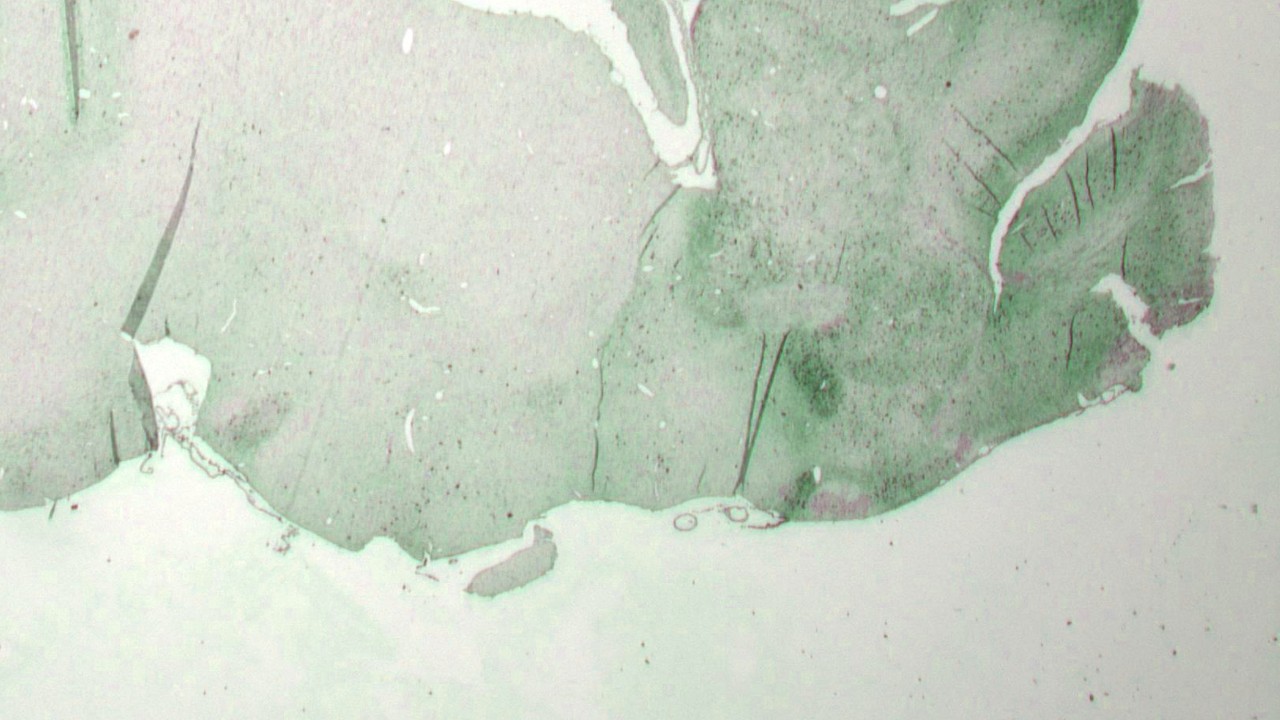

药物安全性和有效性动物实验